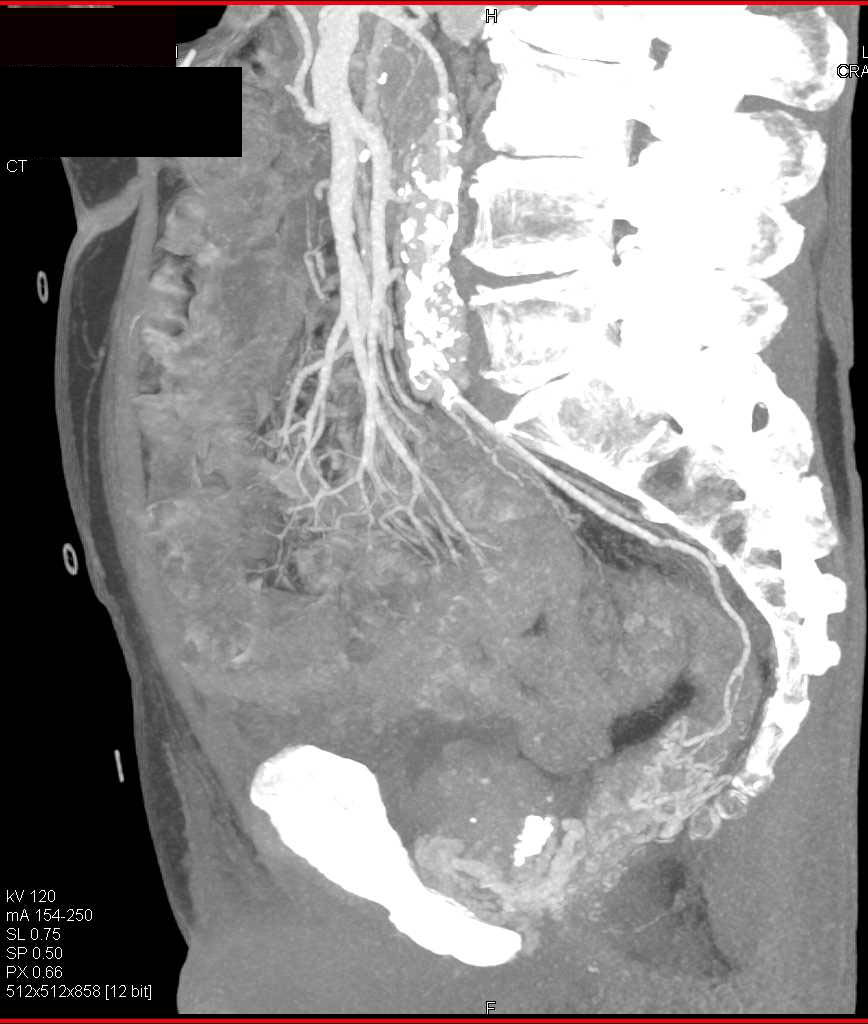

Neurofibroma in Left Ischiorectal Fossa